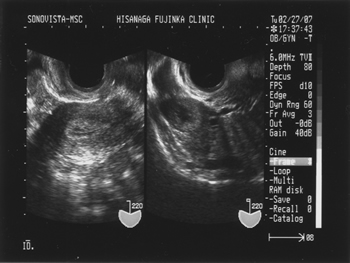

経膣超音波検査(排卵後)・・・排卵により卵巣内の卵胞は黄体に、また子宮内膜は増殖期内膜から分泌期内膜へと変化します。画像でその変化を確認します。まれですが黄体化非破裂卵胞(LUF)といって基礎体温上は高温期になっていても排卵がおこっていないことがあり、排卵がおこったことを確認するためには超音波検査が必要です。

排卵の前後で卵胞は黄体へ、また子宮内膜は増殖期(木の葉状)内膜から分泌期(白く肥厚)内膜へと変化します。

●排卵後●